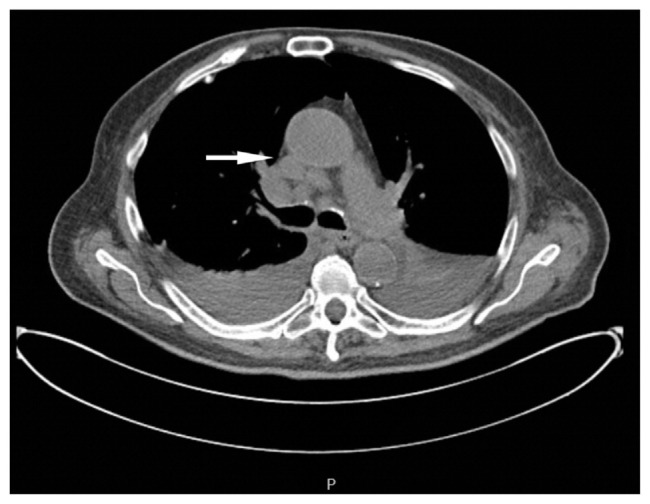

肺癌通常在晚期被诊断出来,经常转移到肝脏、肾上腺、大脑和骨骼等器官。然而,胃肠道转移,特别是小肠,是罕见的。我们报告一个病人谁提出了穿孔的小肠,需要紧急剖腹手术。影像学提示感染过程,但随后的检查显示空肠穿孔和低分化肺癌。尽管有可能接受单独的免疫治疗,病人还是选择了临终关怀。本病例强调了肺癌作为胃肠道并发症的非典型表现,并强调了在鉴别小肠穿孔时保持恶性肿瘤的重要性。

Lung cancer is often diagnosed at advanced stages frequently metastasizing to organs like the liver, adrenal glands, brain and bones. However, gastrointestinal metastasis, especially to the small intestine, is rare. We report a patient who presented with a perforated small bowel, requiring emergent laparotomy. Imaging suggested an infectious process, but subsequent workup revealed jejunal perforation and poorly differentiated lung cancer. Despite being a candidate for immunotherapy alone, the patient opted for hospice. This case emphasizes the atypical presentation of lung cancer as a gastrointestinal complication and underscores the importance of keeping malignancy in the differential for a perforated small bowel.